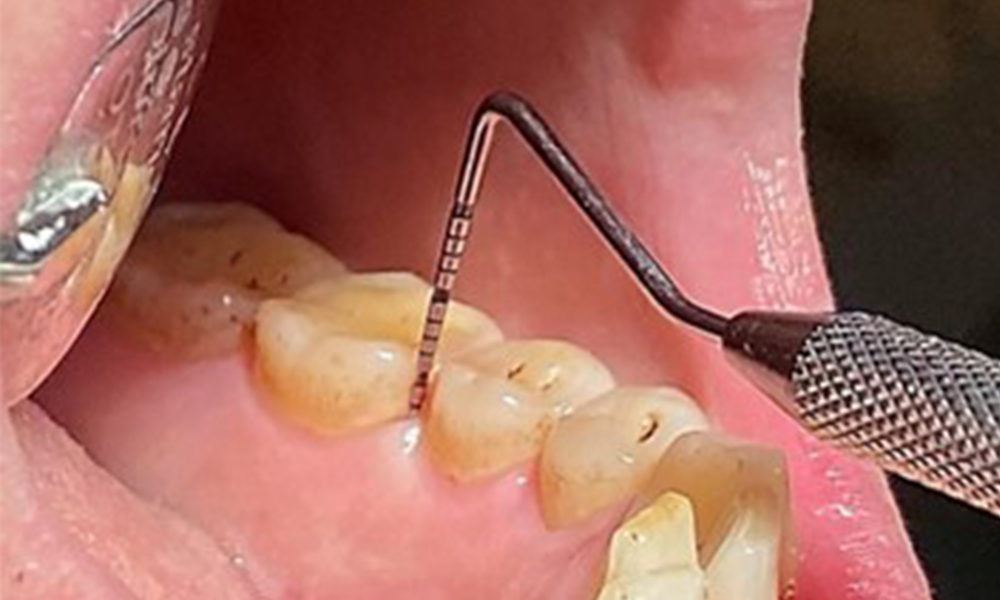

Taschensondierung (BOP) mit Darstellung der Rg. 36 lingual

Abb. 7 Taschensondierung (BOP) mit Darstellung der Rg. 36 lingual, © Dr. R. Krapf

Aufgrund des guten allgemeinmedizinischen Zustandes ist der aus der Mundgesundheit ermittelte Bedarf maßgebend für die Behandlung. Die regelmäßige Erhebung der Sondierungstiefen ist unabdingbar. Die gingivale Blutung ist bei Rauchern herabgesetzt, weswegen die klinische

Diagnose einer Parodontitis nur durch Sondierung möglich ist (Abb. 7). Die ausschließliche Erhebung von Blutungsindizes verdecken unter Umständen das Bild einer bestehenden Parodontitis oder Gingivitis. (5)